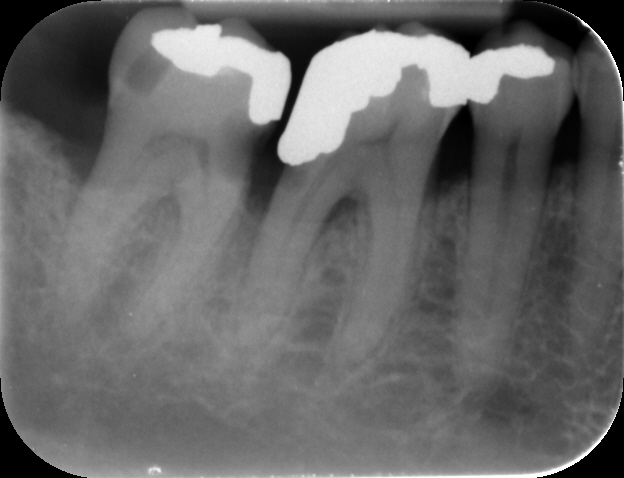

A 57-year-old male patient presented by referral with two failing molars – the LR6 and LR7. The patient had a clear medical history, and both molars exhibited extensive caries and heavy restorations.

Treatment planning

After thorough discussion, the patient was presented with two options: deep marginal elevation combined with root canal treatment or implant placement. The patient opted for implants, expressing a preference for a long-term fixed solution.

Given the absence of acute infection and the availability of adequate bone, we decided on immediate implant placement with delayed loading for both sites. Immediate placement is preferred, as maintaining the existing hard and soft tissue architecture is far more predictable than attempting to rebuild it later.